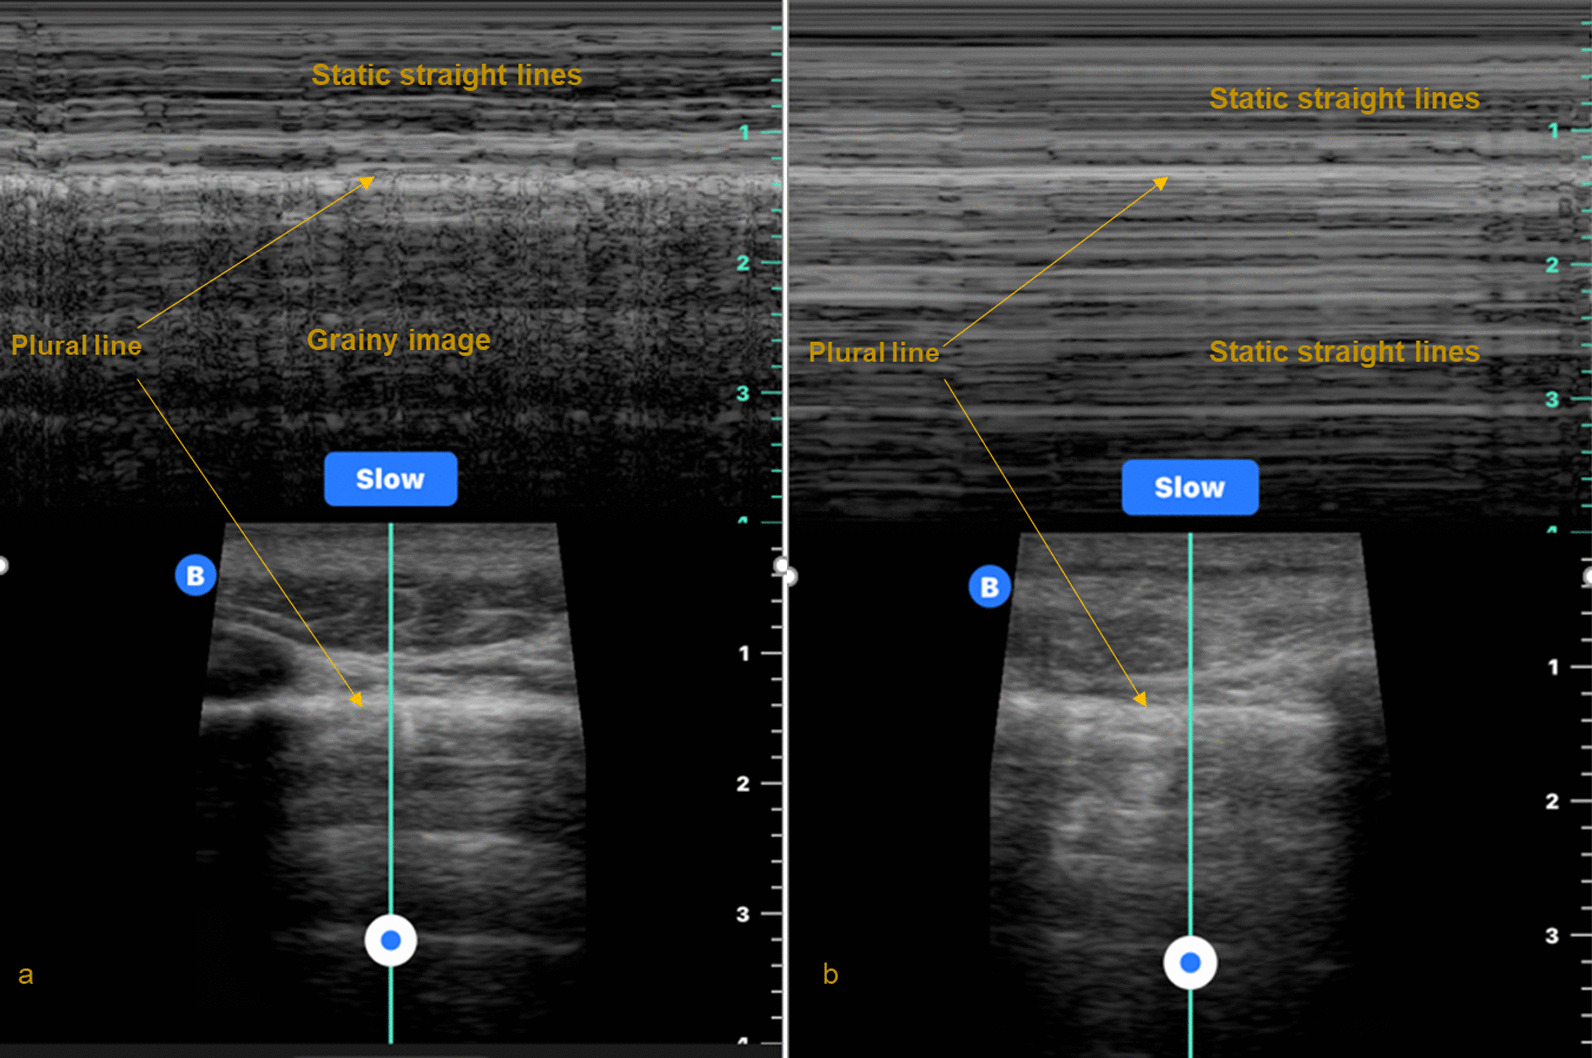

Background: Auscultating for breath sounds to assess for pneumothorax in the helicopter emergency medical services (HEMS) settings can be extremely challenging. Thoracic point of care ultrasound (POCUS) offers a seemingly more useful visual (rather than audible) alternative. This review critically and quantitatively evaluates the use of thoracic POCUS for pneumothorax in the HEMS setting.

Results: Twelve studies reporting on n = 1,936 images from medical and trauma patients were included in qualitative synthesis. Studies were nearly all observational designs. Most images were acquired by nurses or paramedics who were previously novices to ultrasound. The reference standard was predominantly CT. Specificity results were unanimously precise and very high, whereas sensitivity results were imprecise and extremely variable. Meta-analysis of eight studies involving n = 1,713 images yielded pooled sensitivity 61% (95% CI: 27-87%; I2 = 94%) and pooled specificity 99% (95% CI: 98-100%; I2 = 89%). Six studies involving n = 315 images reported practicality. The highest or second highest categorisation of image quality was reported in around half of those images.

Conclusion: Thoracic POCUS is highly specific but has extremely variable sensitivity for pneumothorax when performed in the HEMS setting. This is from purely a diagnostic (not clinical) perspective. Sensitivity increases when only clinically significant pneumothoraces are considered. Case reports reveal thoracic POCUS can appropriately alter treatment and triage decisions, but only for a small number of patients. It appears predominantly useful in mitigating against unnecessary interventions. More research reporting patient focused outcomes is required. In the meantime, thoracic POCUS appears to offer a more appropriate visual alternative to auscultation for breath sounds when assessing for pneumothorax in the HEMS setting.